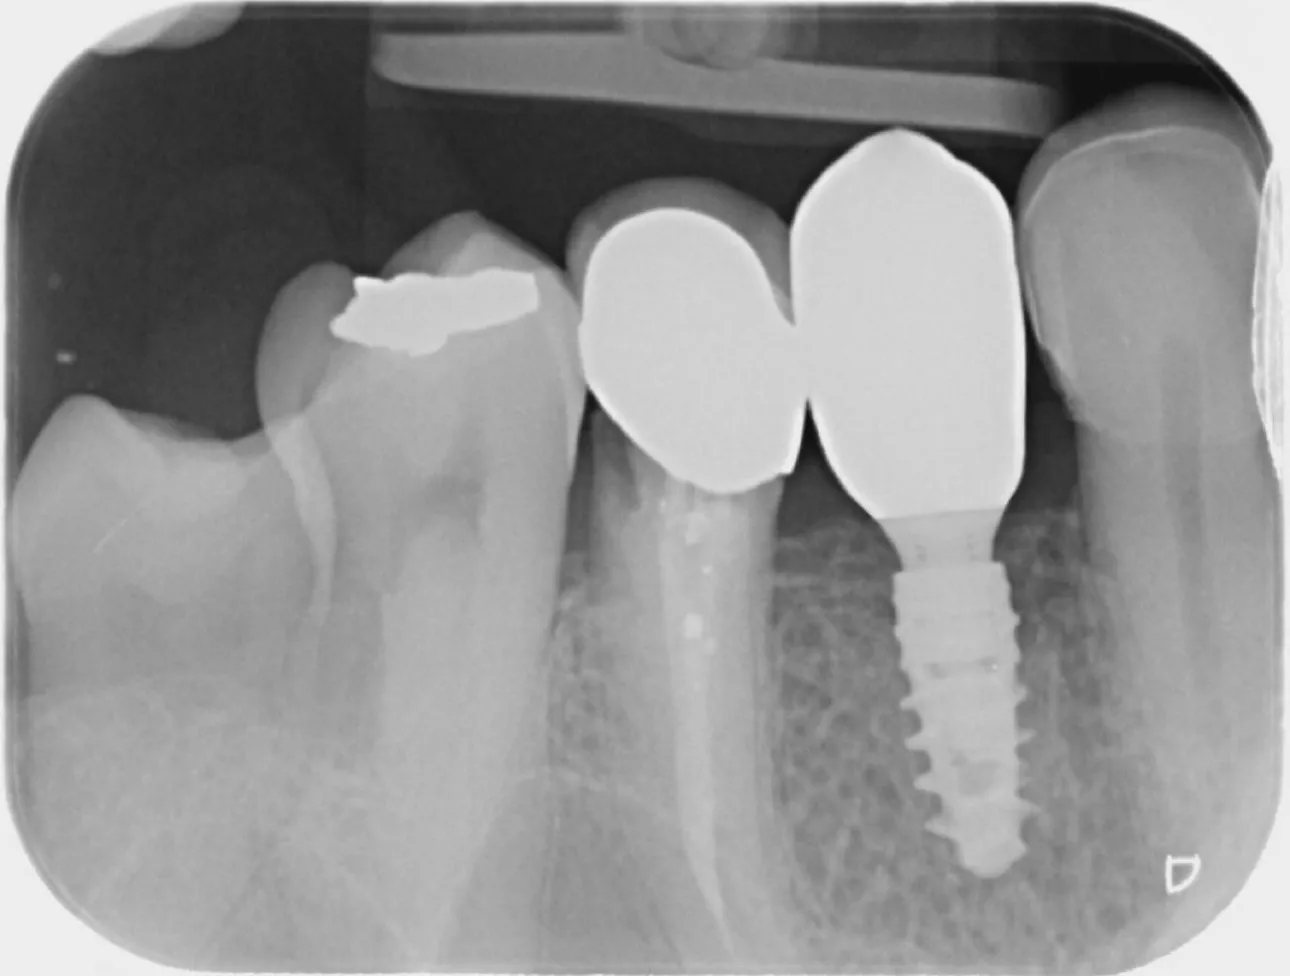

10. Periapical radiograph taken on day 3 post surgery showing the implant with the HealFit® SH healing abutment in position.

10